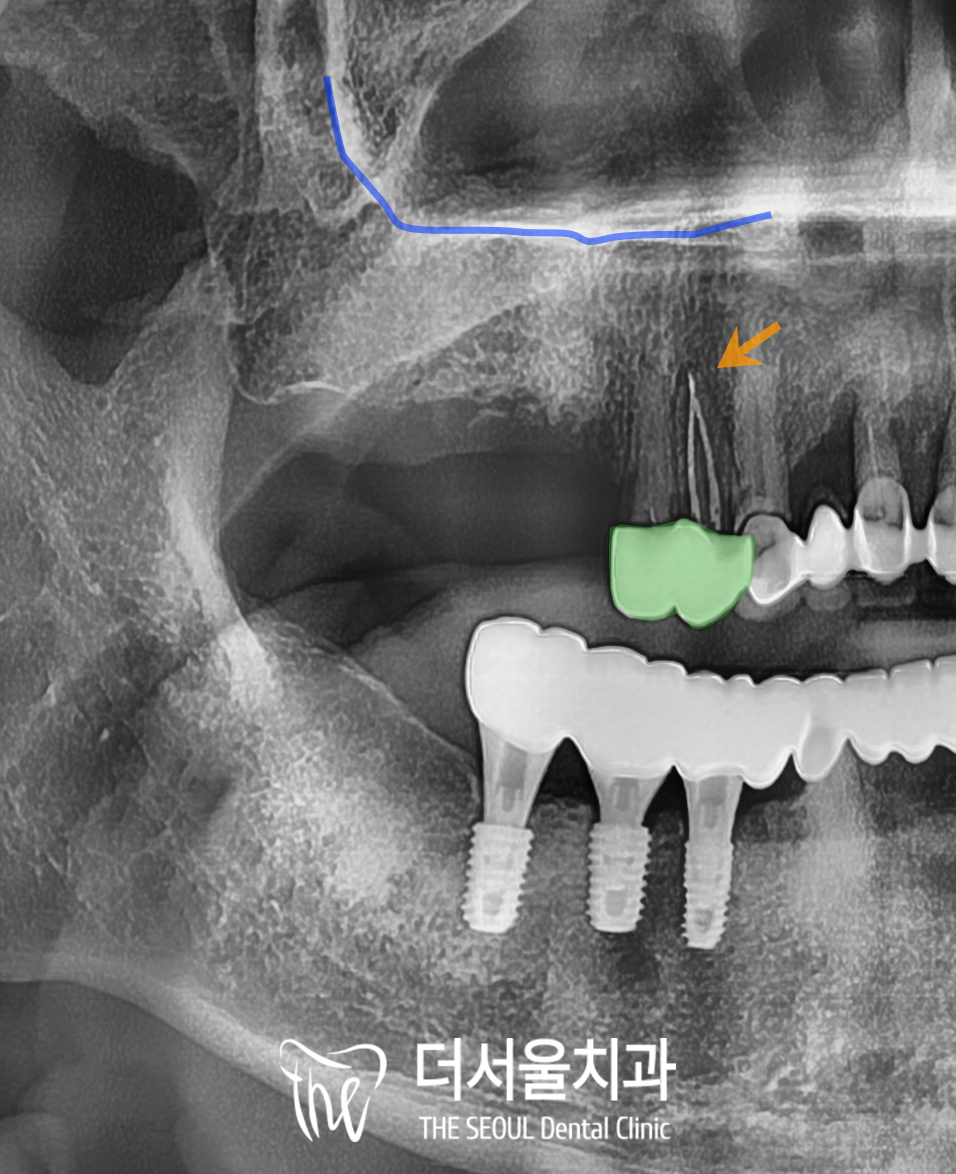

3차원 진단 데이터로

잔존 치조골 높이, 상악동과의 거리,

골밀도 같은 요소를 미리 파악하기에

실제 수술에서는

시술 시간을 단축시킬 수도 있고

불필요한 절개도 막을 수 있어

회복도 훨씬 빠르답니다.

2개월 정도 지나고 이식한 인공뼈의

유착이 잘 이루어졌다면

픽스처를 식립하게 됩니다.

상악 구치부에는

상악동이라는 해부학적 구조물이 있어

이 곳을 천공시키지 않도록

조심스럽게 심어드렸습니다.